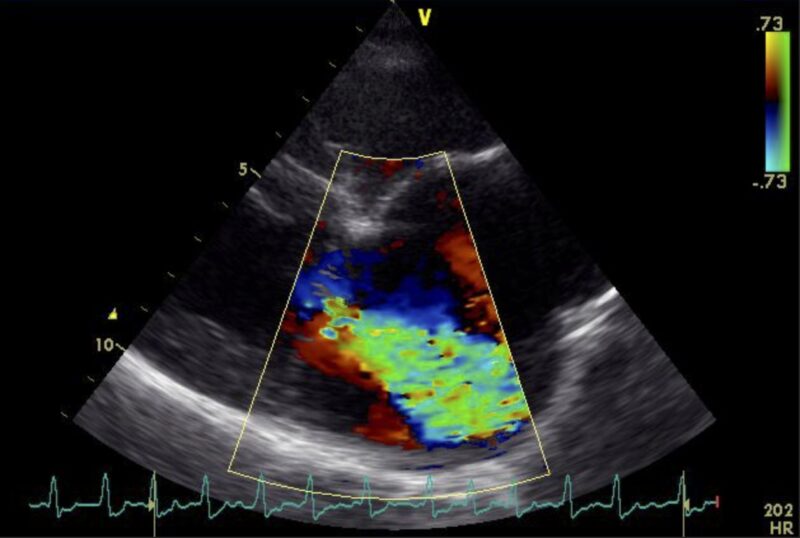

Die Ultraschalluntersuchung des Herzens zeigt letztendlich die Ursache der Veränderungen: Bubbles Herzklappe zwischen dem linken Vorhof und der linken Herzkammer, die Mitralklappe, schließt sich nicht mehr vollständig. Das EKG bei Bubbles ist in Ruhe unauffällig.